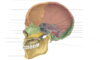

Reconozca la marca ósea encerrada en el círculo

Sutura escamosa